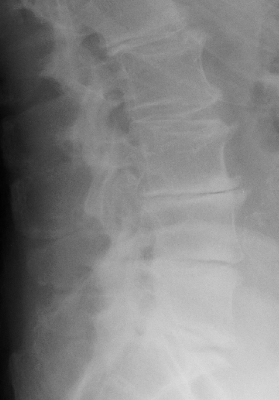

Diagnosis:Degenerative disk disease Discussion:The presence of a linear radiolucency in the disk space (vacuum phenomenon) is a typical finding of degenerative disk disease. It is often associated to other findings of degenerative disk disease such as disk space narrowing and endplate sclerosis. Gas in the disk space is rarely associated to disk space infection. References: